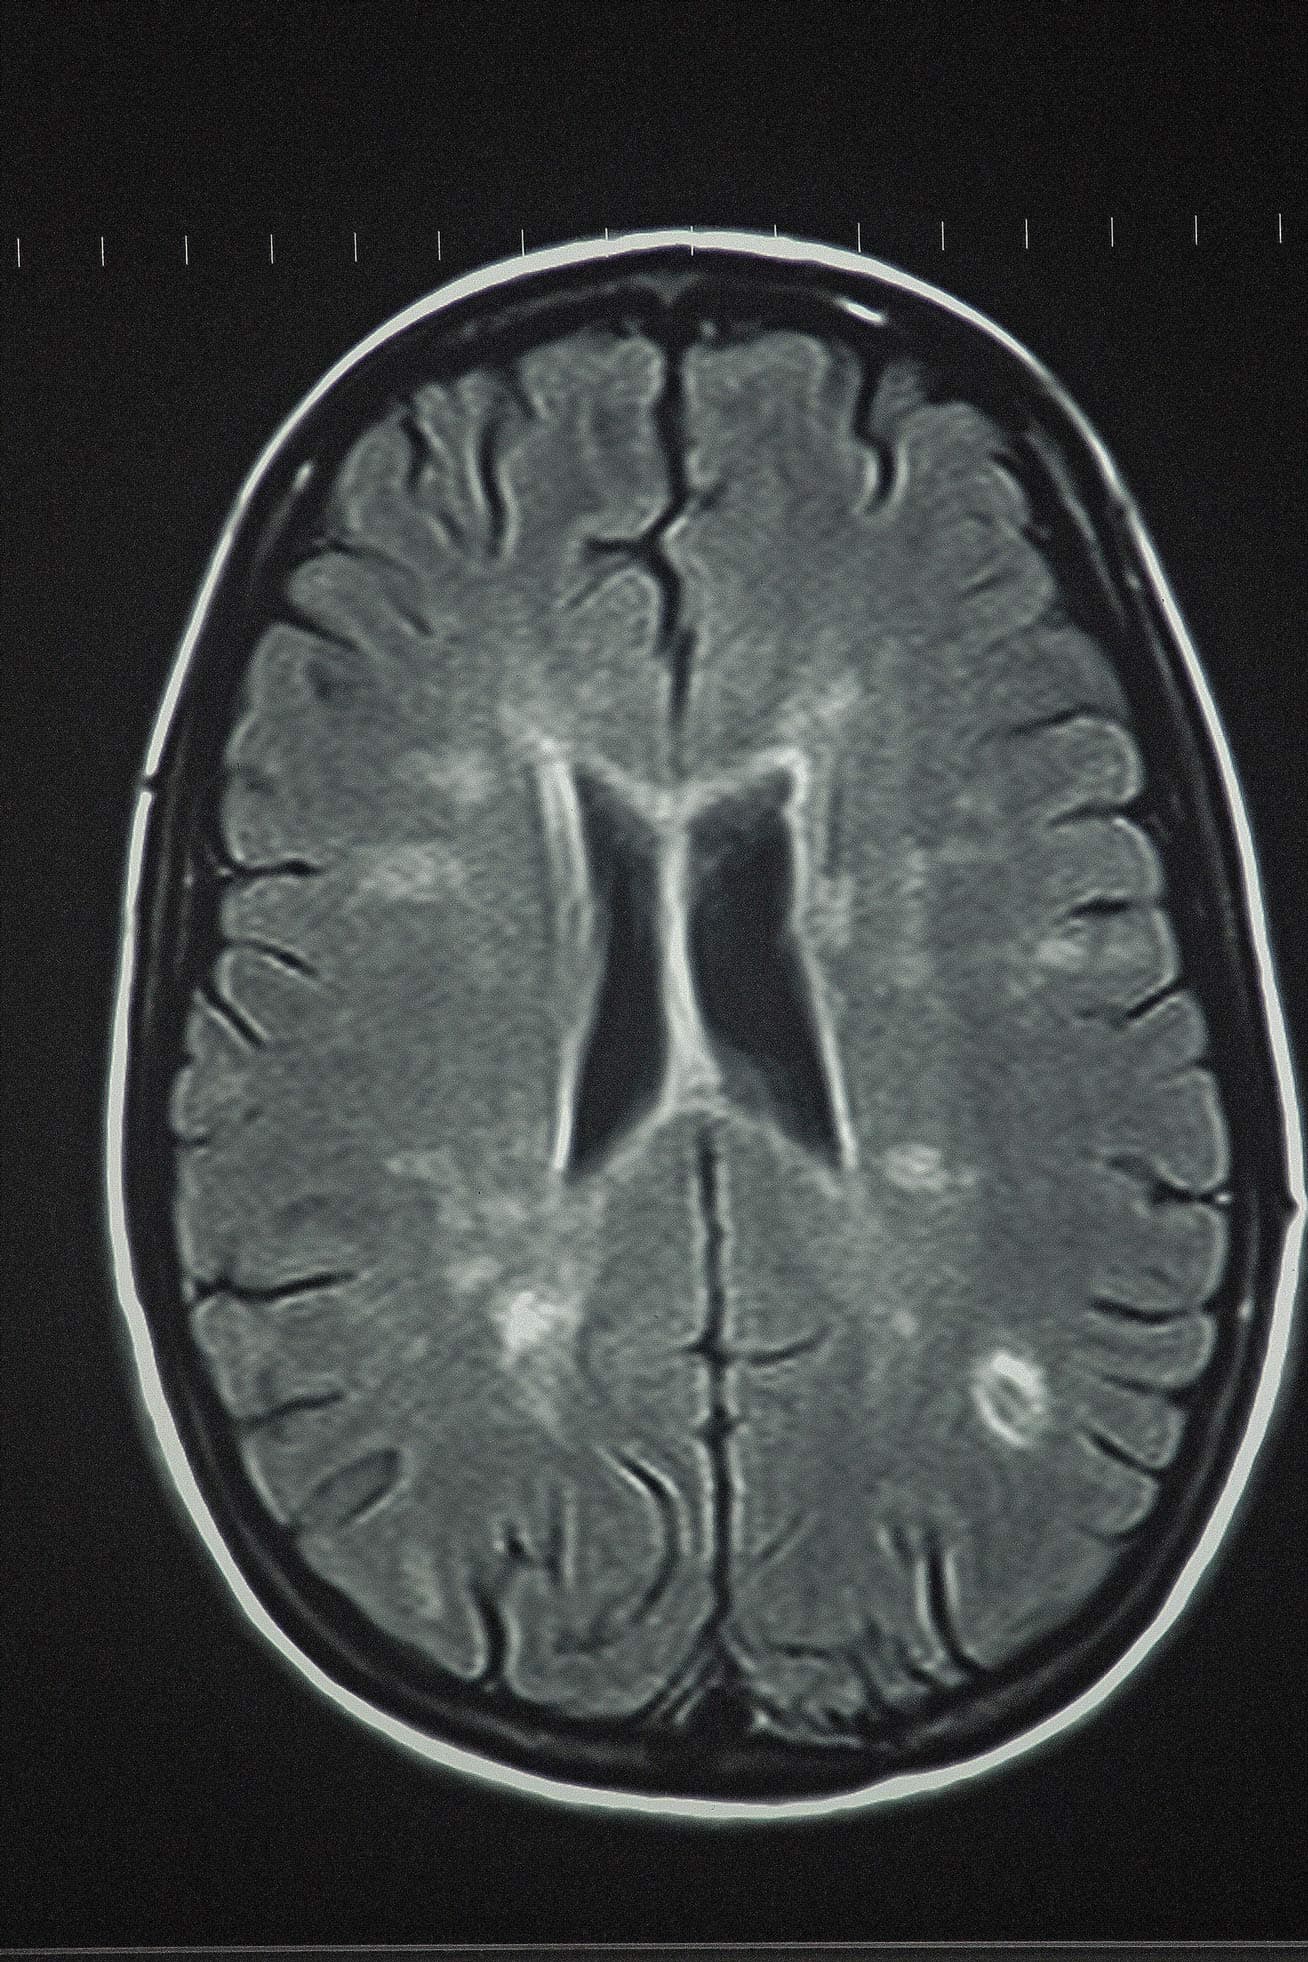

Veränderungen in diesem Netzwerk des Gehirns können mittels MRT sichtbar gemacht werden. Die Topology ist im Ruhezustand (resting state MRI) sichtbar, während die strukturelle Konnektivität mit der diffusionsgewichteten MRT dargestellt werden kann. Auf Basis dieser Daten kann das Netzwerk für den individuellen Menschen rekonstruiert werden.

Aufbauend auf diesen Einsichten untersuchte die deutsche Gruppe in einer randomisierten Studie die Auswirkungen von aerobem Ausdauertraining auf die funktionelle und strukturelle Konnektivität in den Gehirnen von MS-Patienten. Stellmann: „Man könnte unsere Studie als frühe Phase II Studie bezeichnen. Untersucht wurde eine Trainings-Intervention über drei Monate. Die Probanden wurden mit einer nicht-trainierenden Vergleichsgruppe verglichen. Placebokontrolle ist bei Sport schwierig zu erreichen.“ Die Studienpopulation bestand aus 57 Patienten mit schubförmig verlaufender MS mit einem Durchschnittsalter von 39 Jahren und einem medianen EDSS von 1,5. Die Teilnehmer wurden 1:1 randomisiert in eine Vergleichsgruppe und eine Trainingsgruppe, die ein überwachtes und individualisiertes aerobes Trainingsprogramm erhielt. Zu Beginn der Studie und nach drei Wochen wurden MRT-Untersuchungen durchgeführt, aus denen funktionelle Netzwerke rekonstruiert wurden. Dies ergab individuelle Konnektome mit 160 Knoten, die mittels Graph-Theorie auf globaler und nodaler Ebene analysiert wurden. Die Analyse der topologischen Reorganisation erfolgte anhand des adaptierten Hub Disruption Index. Als Referenz dienten die Daten von 30 gematchten gesunden Kontrollen.

Zu Beginn der Studie zeigten beide Patientengruppen im Vergleich zu den gesunden Kontrollen eine höhere funktionelle Konnektivität während die strukturelle Konnektivität geringer war. Beide Effekte waren besonders ausgeprägt in hoch vernetzten Hub-Regionen. Nach drei Monaten war in der nicht trainierenden Gruppe die funktionelle Konnektivität zurückgegangen, während sie in der Trainingsgruppe angestiegen war (p=0.002). Stellmann: „Auf globaler Ebene wurden alle Verbindungen besser.” Auf strukturelle Konnektome wurde ein ähnlicher Effekt gefunden. Während es in der „Waiting Group” keine Veränderungen gab, zeigte die Trainings-Gruppe eine global erhöhte strukturelle Konnektivität (p = 0,002). Veränderungen klinischer Endpunkte wurden nicht beobachtet. Dies sei allerdings, so Stellmann, angesichts des Kollektivs von Patienten mit relativ benigner Erkrankung und der kurzen Beobachtungsdauer auch nicht zu erwarten gewesen.